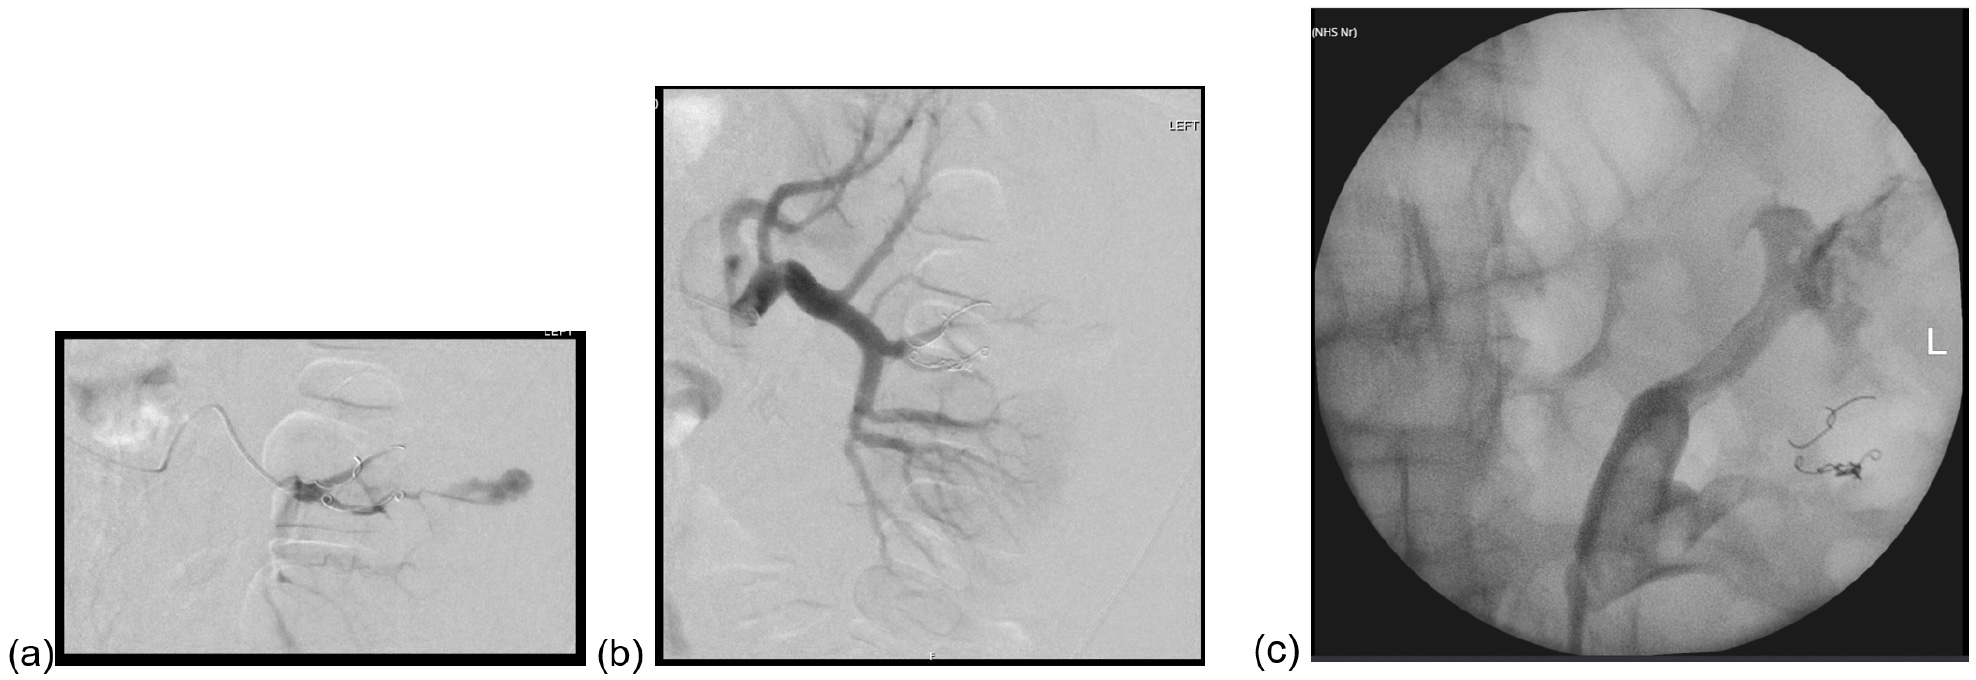

Figure 4: Pre- and post- repeat angioembolisation (a, b) and retrograde showing leak at upper pole (c).

In ICU he continued to require blood transfusions, started spiking fevers, and had ongoing fluid leak from his wound. Repeat CT with a delayed phased showed persisting contrast in the aneurysm despite embolisation, and contrast leak from the collecting system (Figure 3). He was transferred to our department and underwent a repeat angioembolisation, retrograde pyelogram and insertion of ureteric stent (Figure 4). A circumcision was also performed, with histopathology confirming lichen sclerosus. He was discharged eight days after transfer, with a plan to remove the urethral catheter and ureteric stent at three weeks and three months respectively.